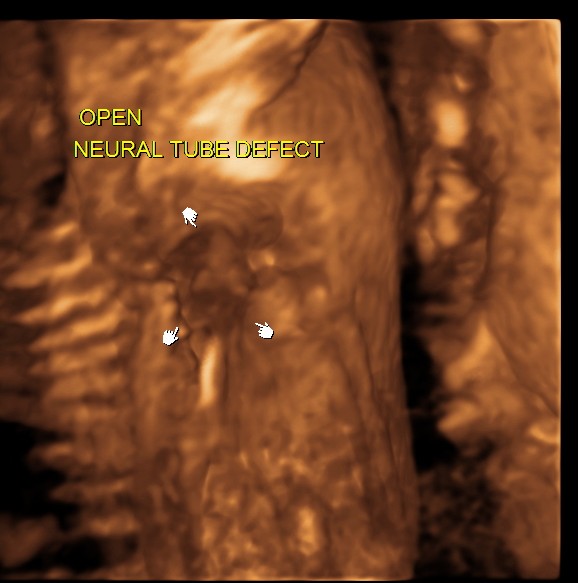

the next is a 3 d image of the open neural tube defect in the thoracic region

the following images are reconstructed images.